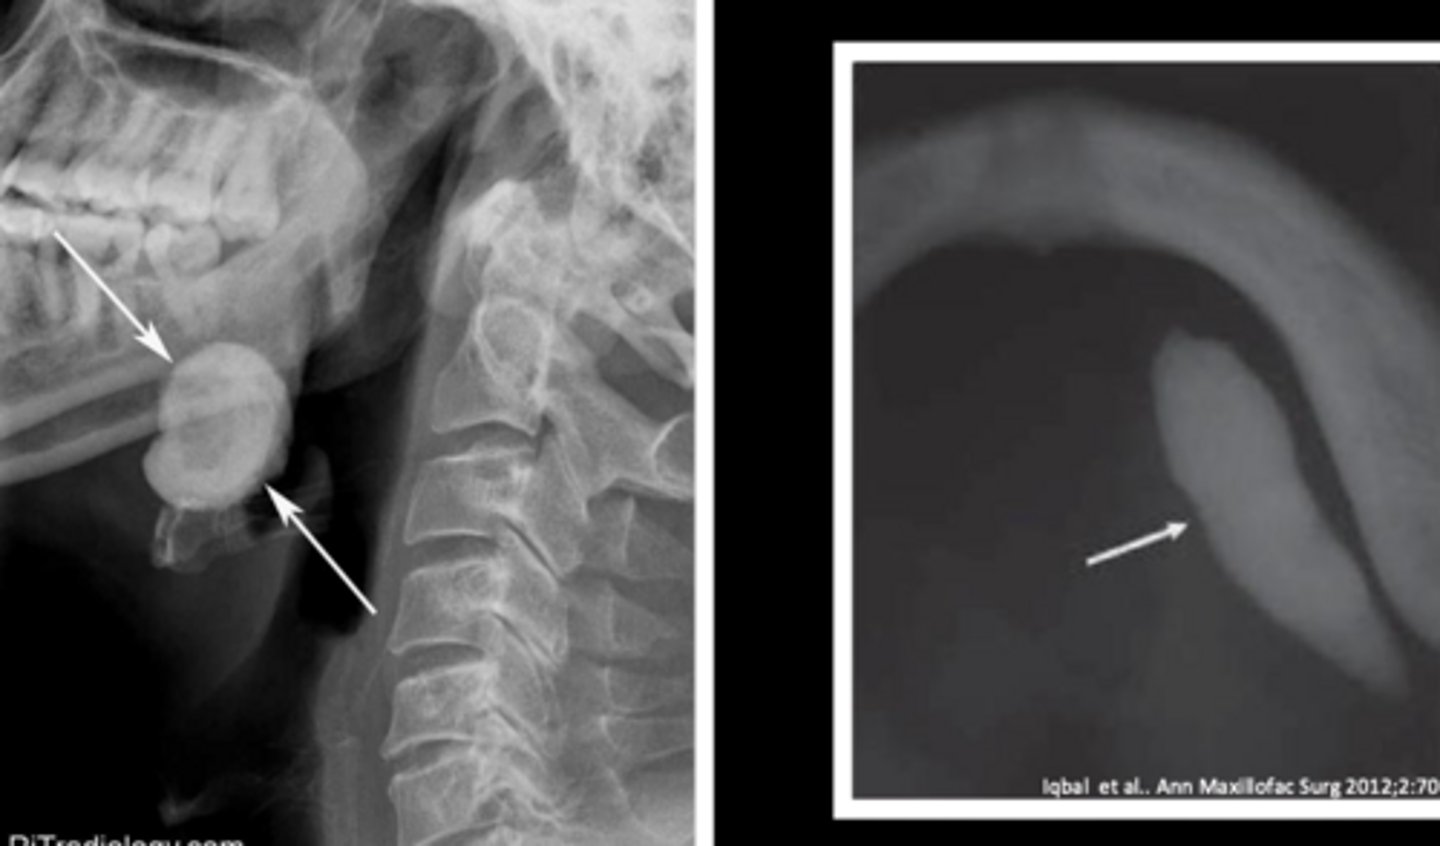

what is the calcified, round, yellow, hard mass structure within the salivary ductal system caused by the deposition of calcium salts around a nidus of debri within the lumen?

sialolith

what reactive salivary gland lesion most commonly occurs in the submandibular gland/duct due to the tortuous path of Wharton's duct and may be firm/hard?

sialolithiasis

what reactive salivary gland lesion causes pain and swelling during times of increased salivation?

(t/f) sialoliths appear as radiolucent masses on radiographs

false; sialoliths appear as radiopaque masses on radiographs

how are small sialoliths treated? how are large sialoliths treated?

milking the stone out; need surgical removal (entire gland may need to be removed)

what reactive salivary gland lesion is treated with sialagogues, moist heat, and fluid intake to promote passage?